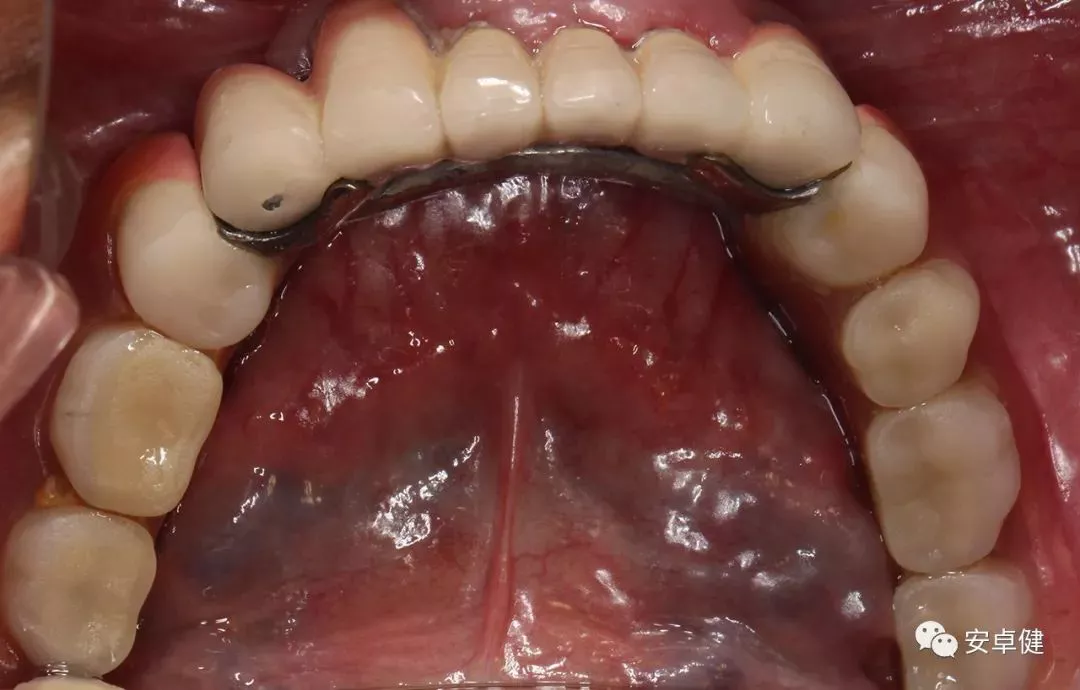

最终修复体合面照

最终修复复诊合面观

戴最终修复体合面观